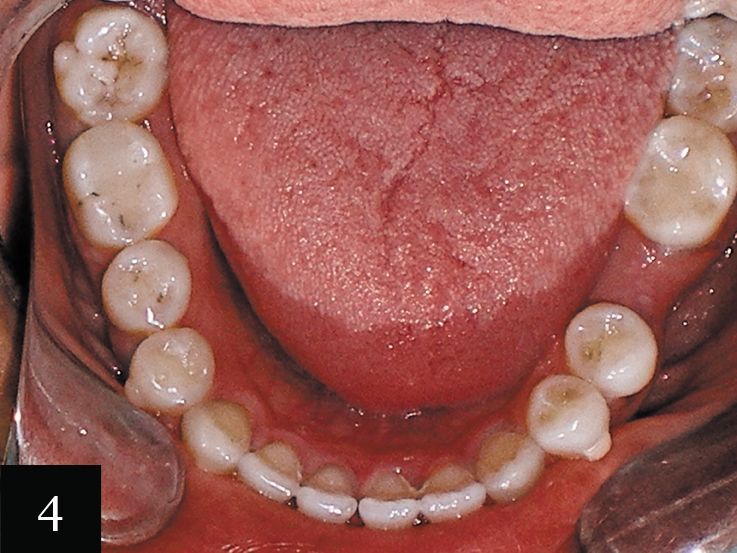

Case No. 1

This patient was a 55-year-old woman with a large space in her lower arch (Fig. 1). Despite this space, the patient was not missing any teeth. Figure 2 shows the impression-taking challenge-capturing the distal edge of the molars while also capturing the forward angle of the front teeth.

The impression was successfully captured on the first try, and the patient was treated with a series of 32 aligners over 16 months. The final result shows the closed space in the mandible and the dramatic esthetic improvement (Figs. 3 and 4).